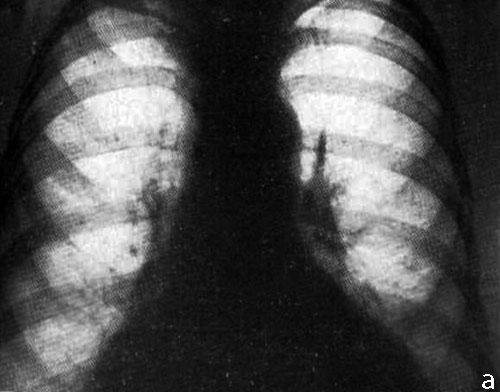

после детальной оценки предоставленной вами рентгенограммы вижу следующие изменения :в S3 верхней доли правого легкого определяется участок гиповентиляции(гипоателектаз) со сближением элементов легочного рисунка(сосудов и бронхов), в проекции  субсегментарной ветви правой легочной артерии  опеределяется участок фиброза(причем рискну сказать,что это не пневмофиброз,а утолщение центрального перибронховаскулярного интерстиция).у меня 2 версии возникновения гипоателектаза S3:первая учитывая фиброз -это фиброателектаз(поствоспалительный большой давности),второй это постстенотический -необходимо исключить центральный рак в S3 суб- или сегментарного бронха!!! с уважением федя

ИМХО: справа в S3 было и сохраняется уплотнение лёгочной ткани перибронхиального харктера, которое с учётом клиники, можно раcценить как проявление пневмонии, которая в настоящий момент клинически разрешилась.Только вопрос какого характера пневмония -банальная или вторичная, параканкрозная остаётся открытым.Показана РКТ ( если недоступна, то как суррагат последней  срединная линейная томография, на проходимость бронхов) + бронхоскопия. Я бы ещё постарался поднять ФЛО-архив- не нравится низкое расположение малой междолевой плевры в медиальном отделе, за счёт чего это произошло?- уменьшение в объёме средней доли? ( если-да, то когда это возникло сейчас или давно?) или вздутие S3? Если ничего не сделают и выпишут пациента, то в случае варианта, что пневмония была на фоне нарушения проходимости бронха опухолевого генеза, следут ожидать скорого рецидива пневмонии.

Просто, возможно я ошибаюсь, скорее врего ошибаюсь, но я не вижу на представленных изображениях ни скиалогических признаков пневмонии, ни скиалогических (прямых, или косвенных) признаков центрального рака.

И, у меня возникает законный вопрос, о том, какую пневмонию лечили?